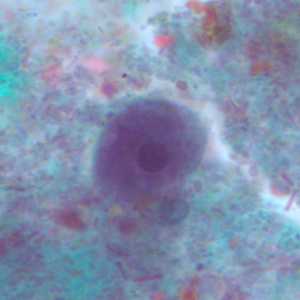

Figure A: Cyst of I. buetschlii stained with trichrome. In this specimen, both the nucleus and large glycogen vacuole are visible.

Figure B: Cyst of I. buetschlii stained with trichrome. In this specimen, both the nucleus and large glycogen vacuole are visible.

Figure C: Cyst of I. buetschlii stained with trichrome. In this specimen, both the nucleus and large glycogen vacuole are visible (arrow).

Figure D: Cyst of I. buetschlii stained with trichrome. In this specimen, both the nucleus and large glycogen vacuole are visible.